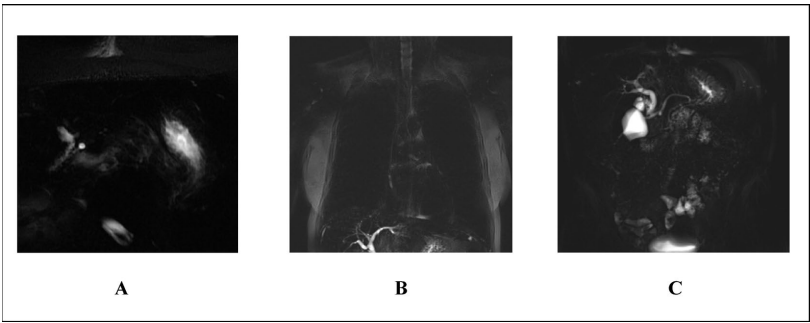

在杜克肝脏数据集的测试中,经过类别标签调整后,模型在7种脉冲序列上的体积级准确率达96.99%,方位分类达99.26%,对比状态分类达97.86%。特别值得注意的是,MRCP(磁共振胰胆管造影)序列因常为单层厚片投影,缺乏空间上下文,成为主要错误来源之一。